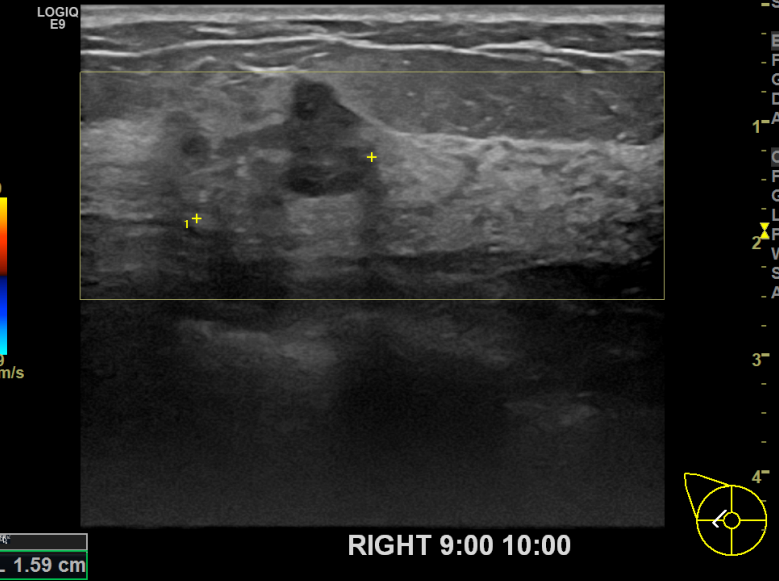

상기환자 외부검진상 이상소견으로 조직검사권유받고 내원하신 50대 여성분으로 우

측유방멍울 조직검사 시행 후 유방암 진단되었습니다.